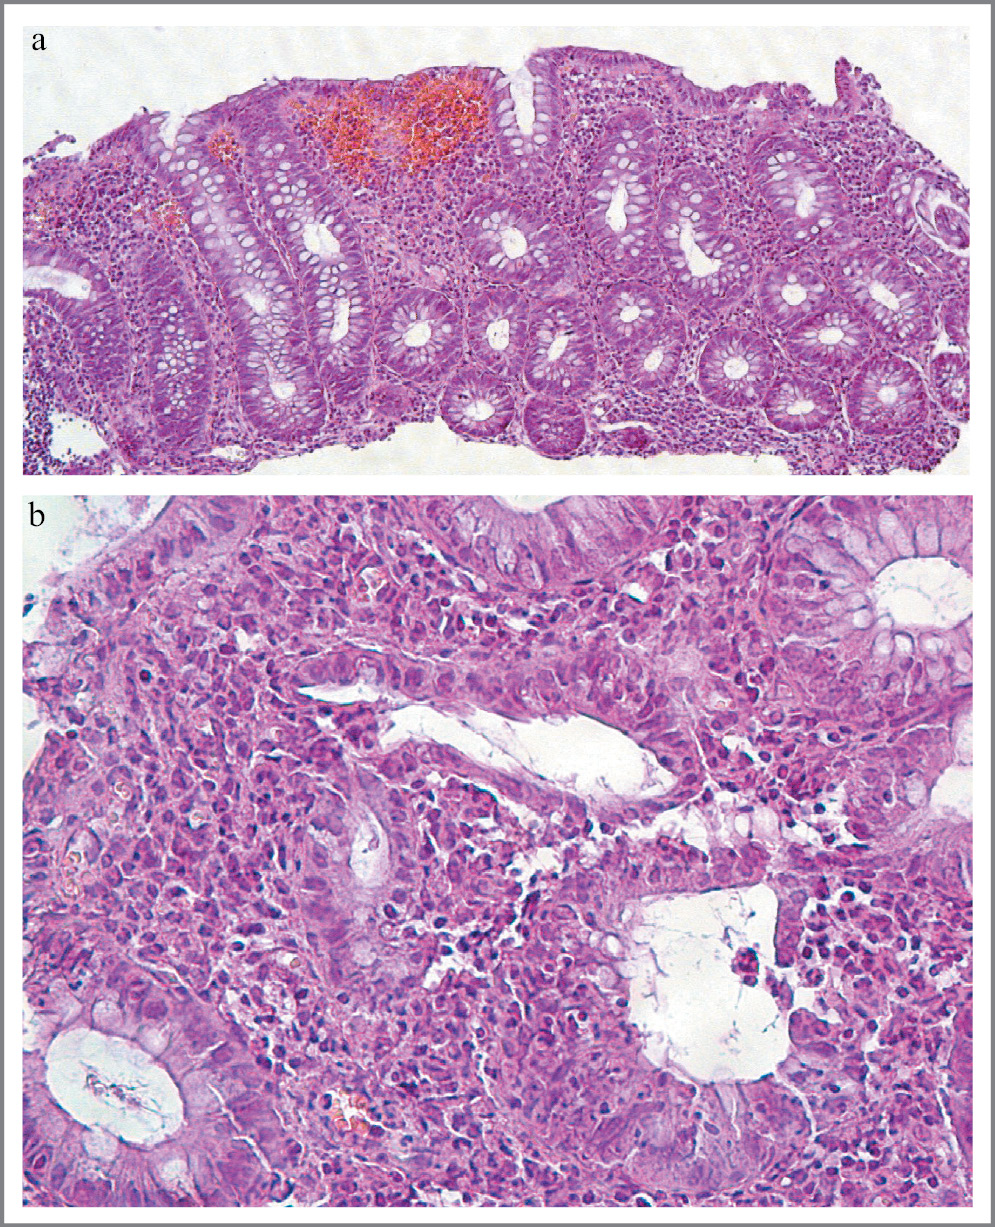

У большинства пациентов имелись структурные нарушения крипт (укорочение, деформация, уменьшение количества и/или неравномерное распределение бокаловидных клеток), отмечались хроническая слабо или умеренно выраженная воспалительная лимфо-плазмоклеточная инфильтрация и базальный плазмоцитоз (очаговый или диффузный) собственной пластинки СОТК. При этом они выявлялись в сочетании со структурными нарушениями крипт, в составе инфильтрата обнаруживались нейтрофильные лейкоциты. Также было характерно повышенное содержание в нем эозинофильных лейкоцитов, местами проникающих в покровный эпителий и эпителий отдельных крипт (рис. 1).

Рис. 1. ЯК, умеренная активность: а – дистрофия и участки десквамации поверхностного эпителия. Количество бокаловидных клеток снижено. Умеренная инфильтрация собственной пластинки, ×120; b – нейтрофилы между клетками эпителия и деструкция отдельных крипт, ×500. Окраска гематоксилином и эозином. / Fig. 1. Moderate ulcerative colitis: a – dystrophy and desquamation of surface epithelial cells. Decrease of Goblet cells. Moderate infiltration of lamina propria, ×120; b – neutrophils between epithelial cells and destruction of crypts, ×500. Hematoxylin and eosin staining.

Обнаружение единичных нейтрофилов в составе инфильтрата или интраэпителиально в покровном эпителии не учитывалось.